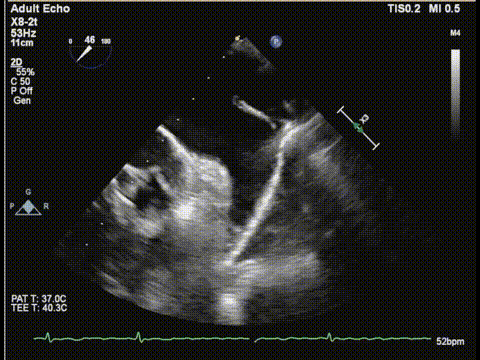

术前食道超声:

房颤,瓣环扩大的房性二尖瓣反流,反流主要集中在二区,二区后叶部分脱垂,后叶的长度16mm,前叶的长度是37mm。房间隔整体的条件可,从瓣环到拟定的卵圆窝顶部高度大概是41mm。

二尖瓣2区

二尖瓣2区color